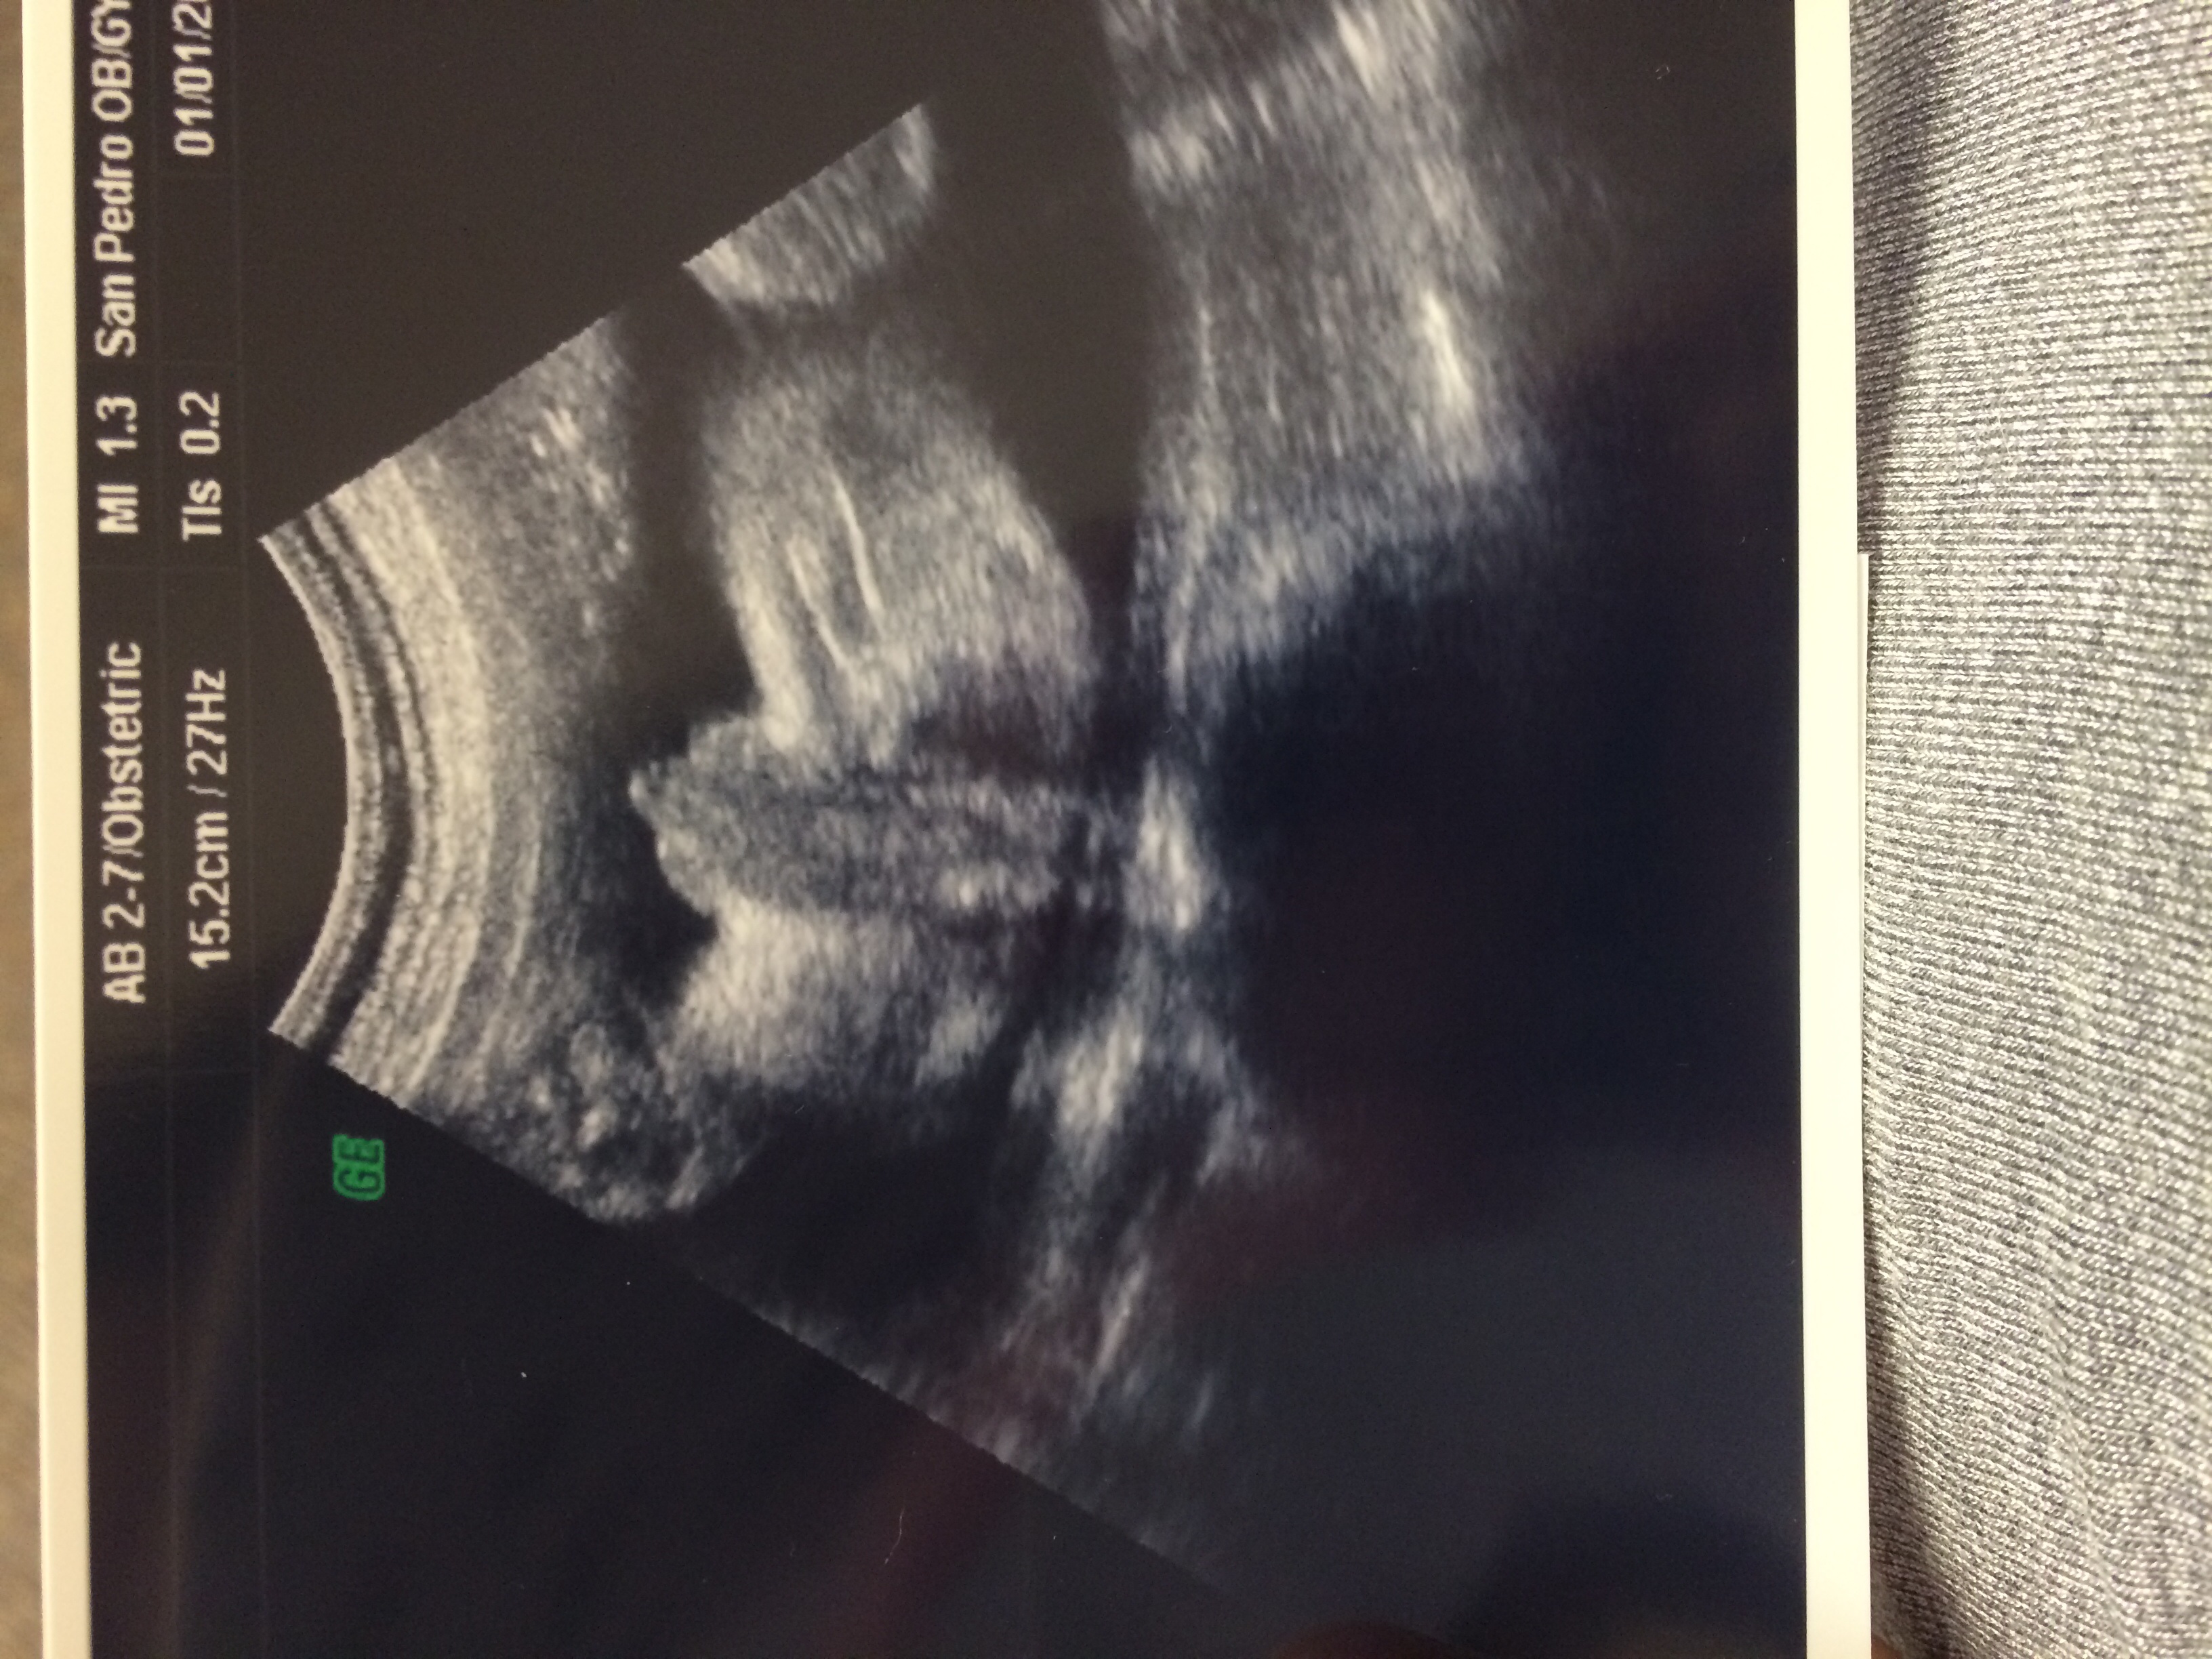

Boy @ 29 weeks

I've been told girl throughout this pregnancy I did have maybe a boy at my anatomy scan and the 2 ultrasound techs weren't sure but were leaning toward boy just wouldn't say for sure. & I have had multiple ultrasounds saying girl but Today at 29 weeks My ob said boy and e has a "short penis" which is normal I guess. I Would love a boy but I'm just confused Attachment 24787

Thats a boy its just the angle. If you were to see it from the side it would look different and maybe longer.

At 29 weeks that is a boy, 100%